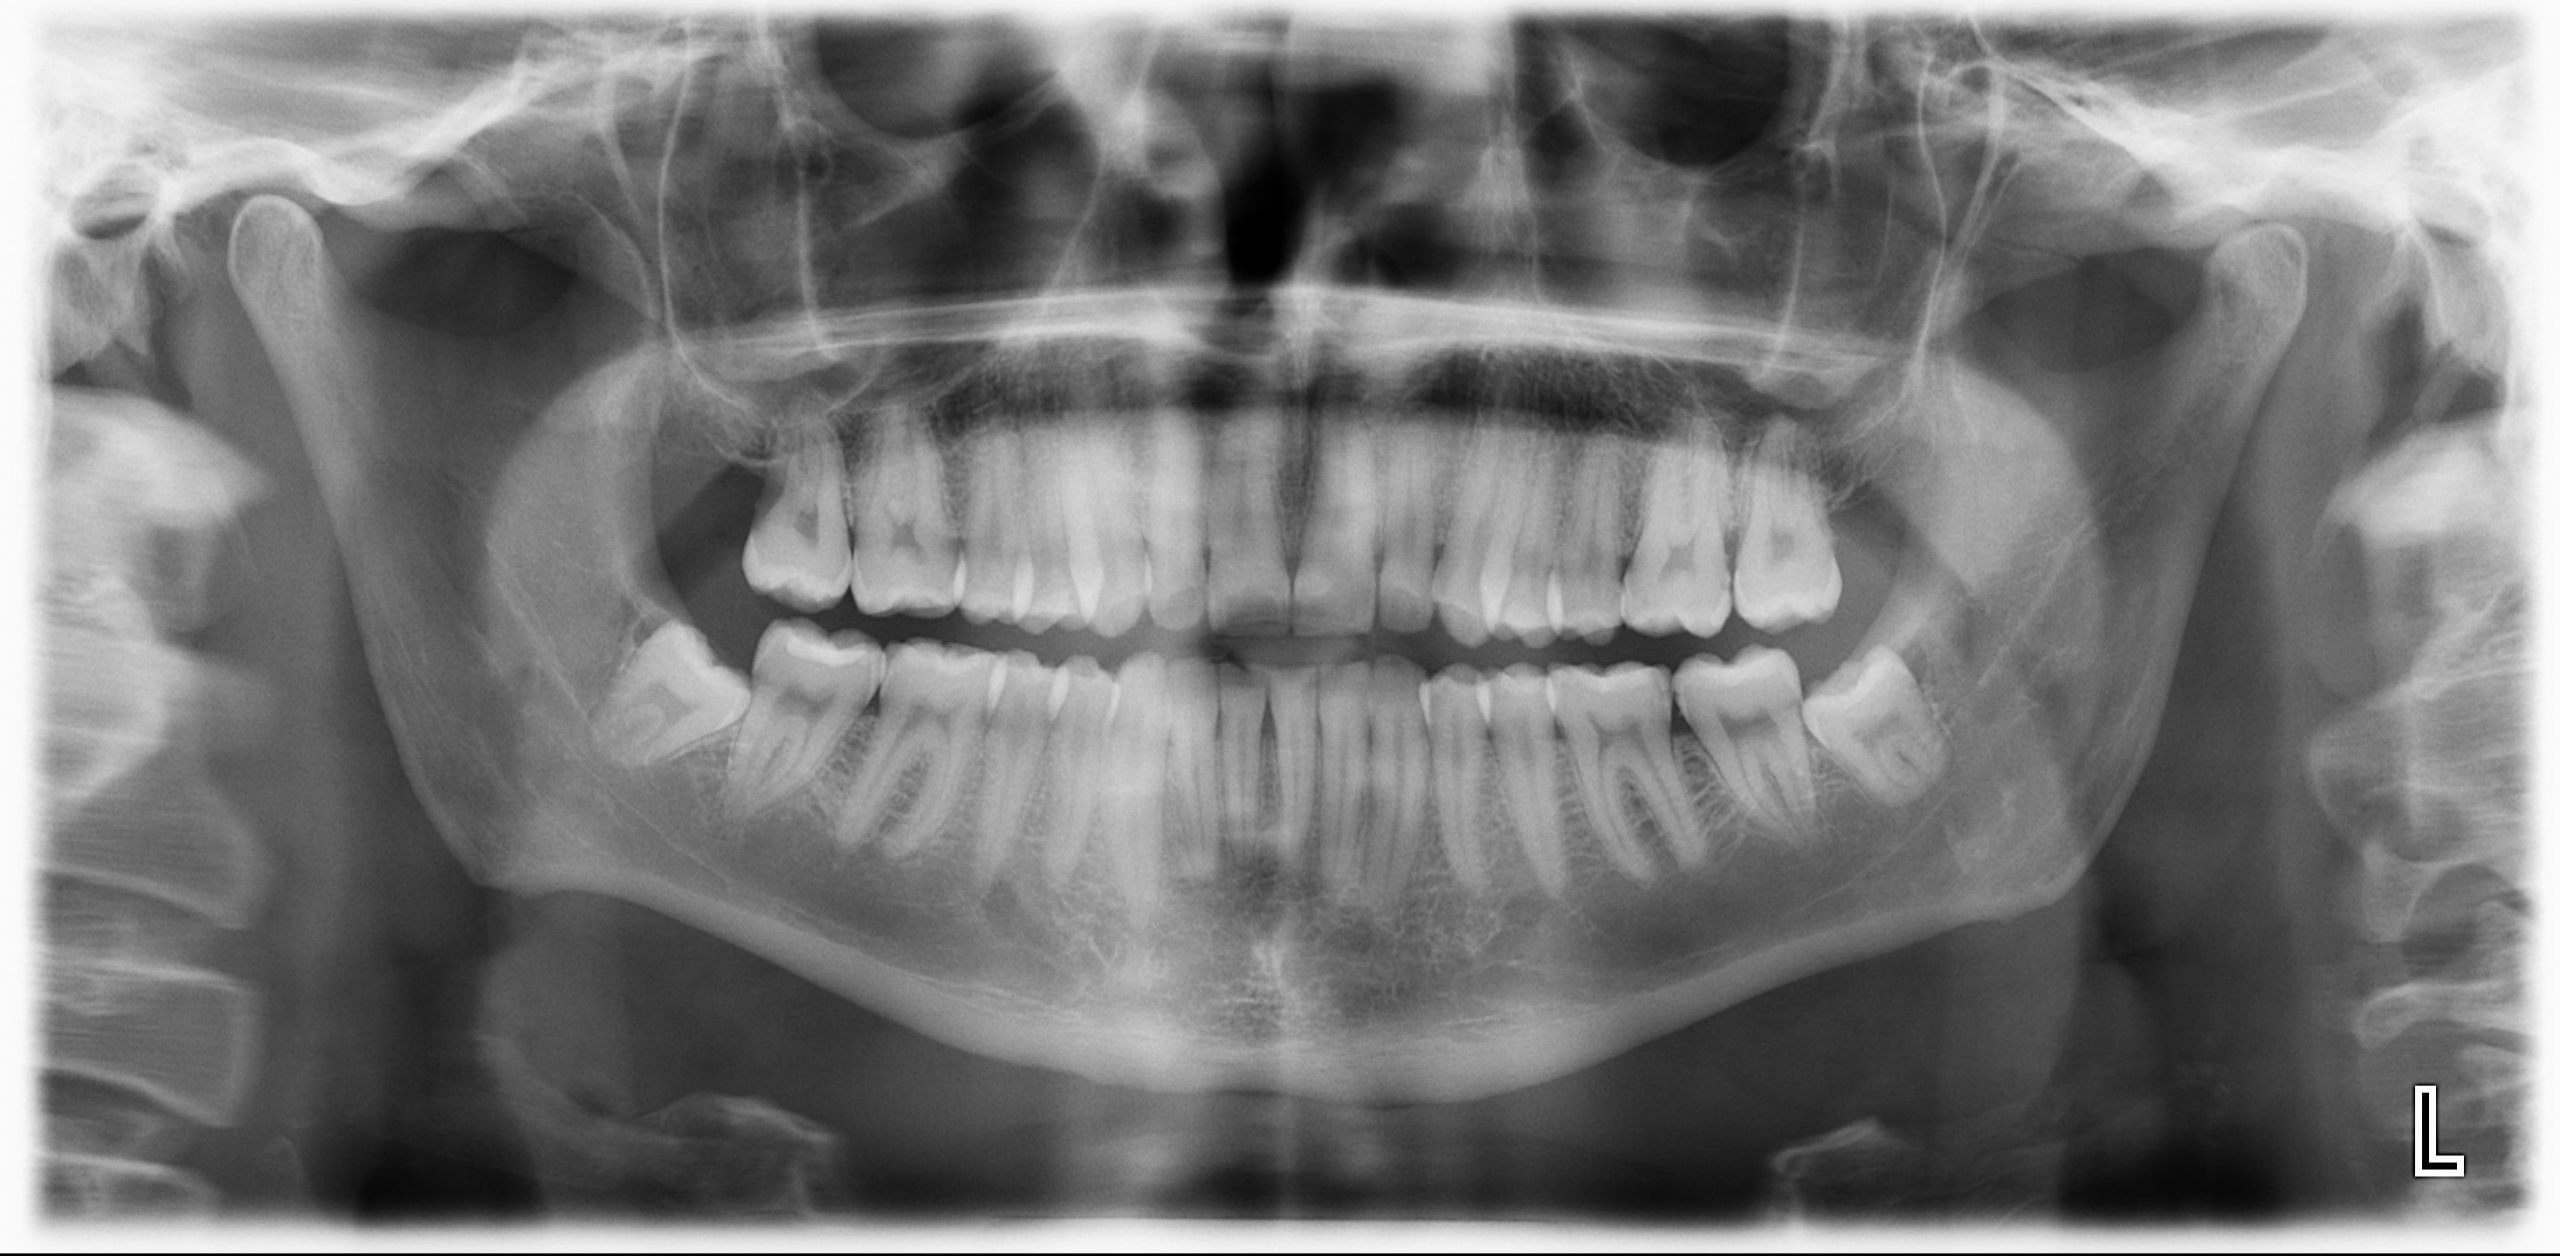

Las intraorales son las radiografías de un conjunto de dientes o un diente en concreto, mientras que las extraorales son la Ortopantomografía muy utilizada para diferentes diagnósticos y la Teleradiografía Lateral de Cráneo para estudios de ortodoncia.

En la ortopantomografía o panorámica vemos todas las estructuras de la cavidad oral